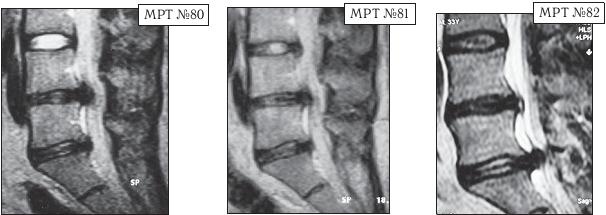

В январе 2002 года пациенту сделали МРТ (№ 77). Мануальный терапевт, проводивший данное лечение, ознакомившись с результатами обследования, объяснил, что в связи с наличием протрузий и грыжи межпозвонковых дисков дальнейшее применение мануальной терапии противопоказано, а также противопоказаны вытяжение позвоночника, йога, интенсивные нагрузки и т. д. В общем-то дал рекомендации, на удивление, довольно грамотные. Только непонятно в таком случае, почему он до лечения не провёл диагностическое обследование пациента и почему продолжал применять мануальную терапию после явного ухудшения состояния пациента?!

Иллюстрация к книге — Остеохондроз для профессионального пациента [i_109.jpg]

На MPT № 77 от 2002 года, наблюдается выраженный дегенеративно-дистрофический процесс, осложнённый протрузиями в сегментах LII—LIII, LII—LIv, LV—SI и грыжей межпозвонкового диска в сегменте LIv-Lv.

На МРТ № 78 от 2007 года отмечается прогрессирование дегенеративного процесса, снижение высоты межпозвонковых дисков, увеличение грыжи межпозвонкового диска в сегменте LIv-Lv.

На МРТ № 79 от 2010 года наблюдается дальнейшее прогрессирование дегенерации и образование секвестрированной грыжи межпозвонкового диска с каудальной миграцией секвестра в сегменте LIv-Lv

После медикаментозного лечения в стационаре самочувствие пациента улучшилось. В дальнейшем, по мере необходимости, он подлечивался амбулаторно и два раза лежал в стационаре. После очередного обострения в 2007 году сделали МРТ (№ 78), на котором наблюдалось прогрессирование дегенеративного процесса, но довольно умеренное. Новый год (2010) данный пациент встречал в кругу друзей, где уже другой друг расхвалил ему ещё одного специалиста в области мануальной терапии, который за два сеанса «поднял» его жену. Четвёртого января прошёл один сеанс у этого «специалиста». По словам пациента, ему «стало легче». Пятого января он прошёл ещё сеанс у данного специалиста. Вначале было «легко, хорошо», но вечером того же дня почувствовал боли. Утром встать уже не смог.

Сделали МРТ (№ 79), диагностировали секвестрированную грыжу межпозвонкового диска в сегменте LIV-LV. Надеюсь, что вы, уважаемый читатель, уже сами понимаете, что применение мануальной терапии в качестве лечения данной патологии было серьёзной ошибкой, которая привела к значительным осложнениям. Но тем не менее, этот случай очень показателен в плане адаптативных механизмов и компенсаторных возможностей организма и того, что происходит в случае их срыва. Всё-таки с 2002 года по 2007 дегенерация развивалась под «контролем» и если бы не «друзья» с их «медвежьей услугой», то возможно не было бы таких последствий.

В чём причина в данном случае резкого образования секвестрированной грыжи межпозвонкового диска? Основная причина таится в срыве адаптивных механизмов. Дегенерация в межпозвонковых дисках развивается как бы по спирали, где на каждом её витке срабатывают защитные (адаптивные) механизмы. Организм постепенно включает данные механизмы, которые «тормозят» и берут под контроль этот процесс. Затем подключаются компенсаторные механизмы. Так происходит адаптация и компенсация, постепенно приспосабливающая организм уже к новым условиям существования. Однако когда происходит срыв адаптивных механизмов (мануальная терапия, вытяжение и т. д.), влекущий за собой нарушение компенсаторных возможностей организма, то дегенерация развивается уже не по спирали, а по прямой — происходит её стремительное, бесконтрольное и неуправляемое развитие.